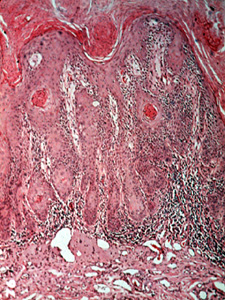

| Se muestran inflamación crónica, "elastosis senil" y displasia del

epitelio con oscuridad anormal agrandada de los núcleos más mitosis,

con este poder de resolución, en la queilítis actínica. |